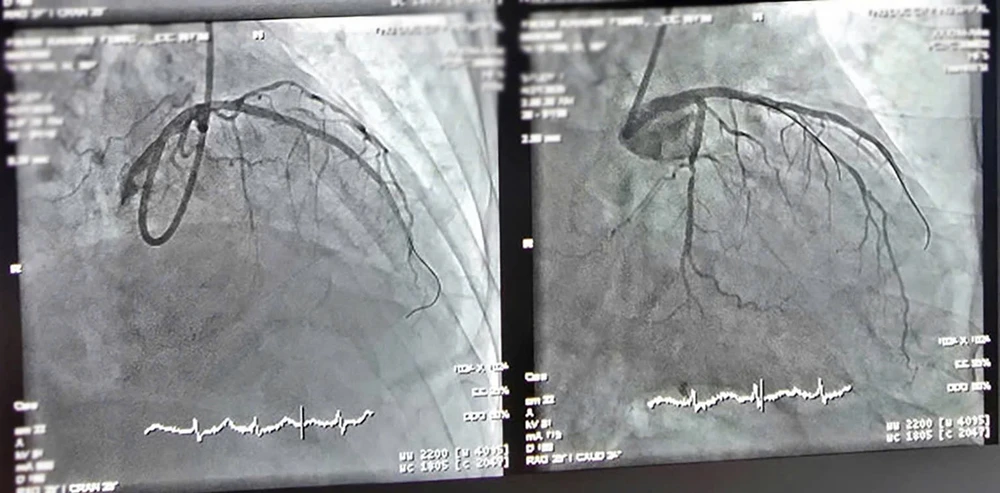

Hình ảnh sau phẫu thuật. Ảnh BVCC

Trước diễn tiến nguy kịch, các bác sĩ đã nhanh chóng tiến hành can thiệp mạch vành, đặt stent tái thông mạch máu thủ phạm mà không gặp biến chứng.

Theo Thạc sĩ, Bác sĩ Đào Quang Hoàng,Phó Trưởng khoa Nội Tim mạch Lão học, đây là ca can thiệp khá phức tạp do bệnh nhân cao tuổi, nhiều bệnh lý nền phối hợp.

“Thêm vào đó, tình trạng mạch máu vôi hóa xơ vữa nặng và cơ địa dễ xuất huyết cũng là thách thức lớn trong quá trình can thiệp", bác sĩ Hoàng nói.